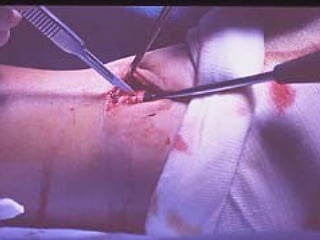

La placca PC.C.P. viene inoltre applicata per via percutanea attraverso due piccole incisioni ottenendo in tal modo un minimo trauma chirurgico ed una  perdita di sangue estremamente ridotta in pazienti che per l’età  sono già in condizioni  critiche

VANTAGGI CHIRURGIA MININVASIVA Mini Open Inserimento della placca sottocutaneo per scivolamento Viti percutanee Preservazione dei tessuti molli Ridotto danno vascolare Rapida ripresa funzionale